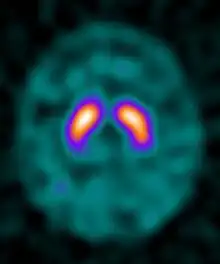

Ioflupane (123I) is the international nonproprietary name (INN) of a cocaine analogue which is a neuro-imaging radiopharmaceutical drug, used in nuclear medicine for the diagnosis of Parkinson's disease and the differential diagnosis of Parkinson's disease over other disorders presenting similar symptoms. During the DaT scan procedure it is injected into a patient and viewed with a gamma camera in order to acquire SPECT images of the brain with particular respect to the striatum, a subcortical region of the basal ganglia.[6] The drug is sold under the brand name Datscan and is manufactured by GE Healthcare, formerly Amersham plc.

Ioflupane has a high binding affinity for presynaptic dopamine transporters (DAT) in the brains of mammals, in particular the striatal region of the brain. A feature of Parkinson's disease is a marked reduction in dopaminergic neurons in the striatal region. By introducing an agent that binds to the dopamine transporters a quantitative measure and spatial distribution of the transporters can be obtained.